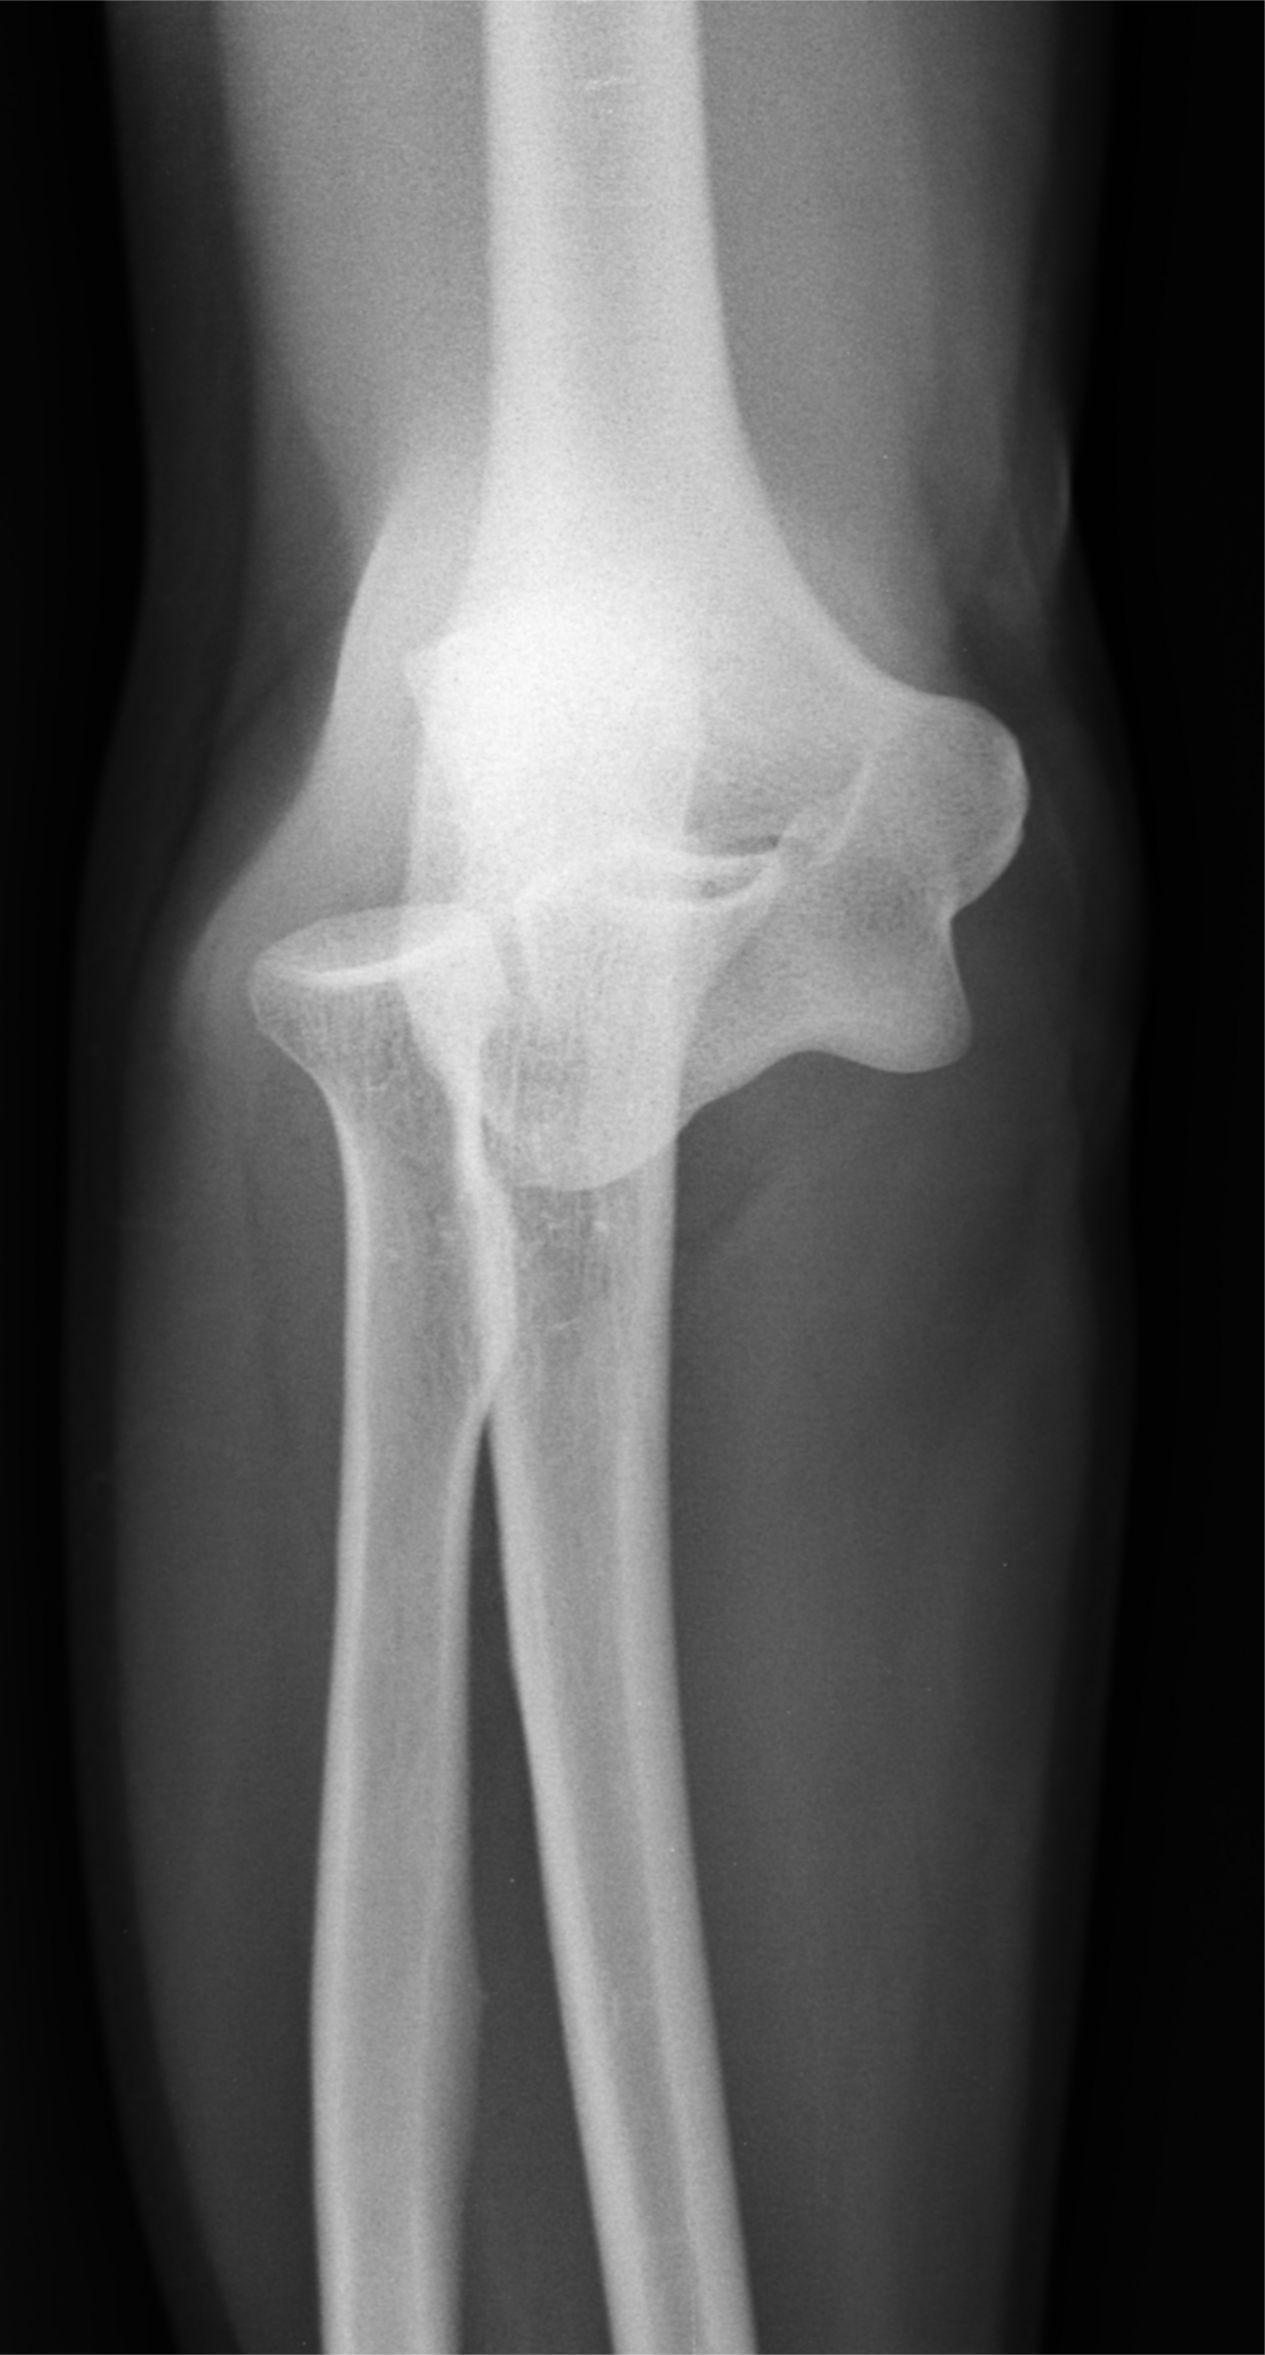

Maulik S Patel, Radiopaedia.org. From the case rID: 20406